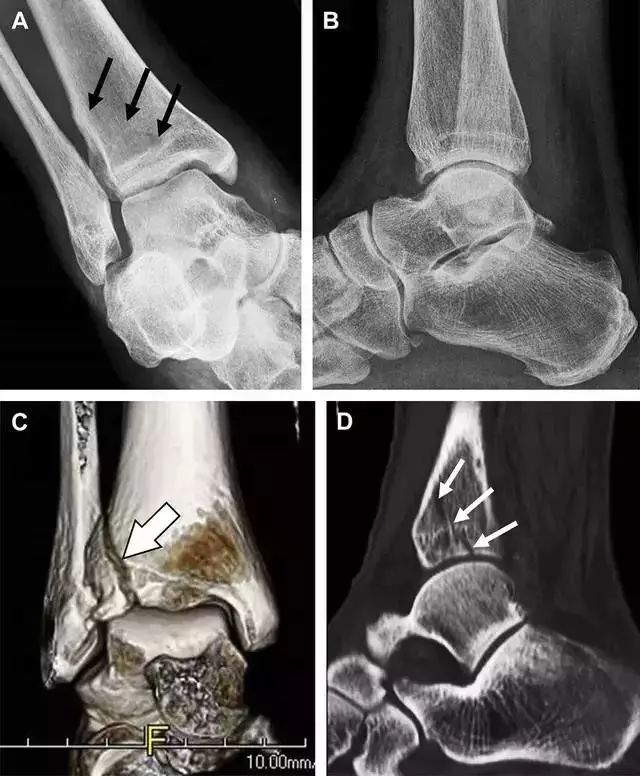

18

距骨外侧突骨折

距骨外侧突骨折常因踝外翻背屈时,跟骨上外侧面撞击距骨外侧突下缘导致,或偶尔由踝内翻引起,被称为「滑雪板者骨折」。这种骨折只能在踝关节正位片上发现,而且外踝远端表面软组织肿胀往往是一个重要线索(图 4)。

图 4 距骨外侧突骨折。A 正位片示内翻损伤所致的距骨外侧突撕脱性骨折(箭头);B 另一位患者,踝外翻损伤导致典型的「滑雪板者骨折」,X 片上可见一较大的三角形骨折块(方框);C 第二位患者的 MRI 矢状位 T1 加权像示横行骨折(箭头)。

19

距骨后突骨折

距骨后突有内侧结节和外侧结节,距骨后突内侧结节撕脱性骨折常发生在背屈内旋的*力暴**作用下。严重跖屈时,胫骨后缘和跟骨挤压距骨后突外侧结节呈楔形,易发生粉碎性骨折。这些骨折细微且需与三角骨鉴别。侧位片观察距骨后突骨折最佳,常规拍片很难发现,当高度怀疑这种骨折又没法做 CT 时,建议加做多个角度的外旋斜位片(图 5)。

图 5 距骨后突骨折。侧位片(A)和 MRI 矢状位 T1 加权像(B)均示后外侧突的简单骨折(箭头),再次阅片时才发现 X 线片上的骨折;侧位片(C)和 CT 横断面图像示后内侧突的粉碎型骨折(箭头)。